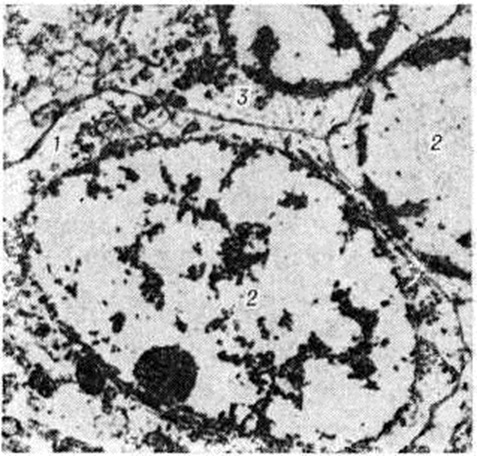

Электронно-микроскопическое исследование коры мозга человека при Инсульт выявляет различные ультраструктурные изменения нейронов, глиальных элементов и капилляров. В ультраструктуре капилляров можно выделить следующие основные патологический изменения: дистрофию стенки капилляра с накоплением в ней лизосомальных включений, липофусциновых гранул, распадом митохондрий, расслоение и вакуолизацию базальной мембраны (рисунок 18). Кроме того, отмечается разрастание и гиперплазия эндотелия. Ультраструктурные повреждения капиллярной стенки сопровождаются разнообразными изменениями из просвета. Обнаруживается ряд изменений основных субмикроскопических компонентов нейронов. Наиболее характерны нейроны, изменённые по гиперхромному типу (рисунок 19), что сочетается с пикнозом ядра, разрушением митохондрий, деструкцией гранулярного и агранулярного ретикулума, наличием большого числа вакуолей и лизосомальных включений, и нейроны с явлениями хроматолиза (рисунок 20), который сопровождается исчезновением цитоплазматических включений, растворением мембранных структур, образованием вместо цистерн ретикулума групп дискретных пузырьков, отсутствием рибосом, набуханием митохондрий, появлением вакуолей. Изменение ультраструктуры капилляров и нейронов сопровождается отёком астроцитарных отростков, скоплением тел глиальных клеток вокруг патологически изменённых элементов. В области расположения патологически изменённого капилляра наблюдаются клетки-тени (клетки в состоянии кариоцитолиза). Прослеживается зависимость изменений элементов одной цепи: нейрон — капилляр — глия.